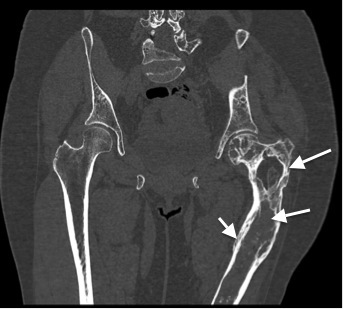

- ПЭТ-КТ, МСКТ скелета в ЭНЦ: в левых отделах лобной кости (рис. 15), в клиновидной кости, теле и левой ветви нижней челюсти определяется расширение границ кости, уплотнение структуры по типу «матового стекла». Также визуализируются участки разряжения и уплотнения 3–6 ребер слева, грудных и поясничных позвонков, S1 позвонка. Аналогичные изменения в проксимальных отделах левой бедренной кости, теле и гребне левой подвздошной кости (рис. 16). Выявленные изменения костей соответствуют полиоссальной форме ФД.

Рис. 16. Пациентка Щ. МСКТ, криволинейная реконструкция.

Полиоссальная форма фиброзной дисплазии. Разряжение структуры костей с сохранением трабекулярного рисунка без деструкции кортикального слоя в проксимальных отделах левой бедренной кости, теле и гребне левой подвздошной кости (стрелки).